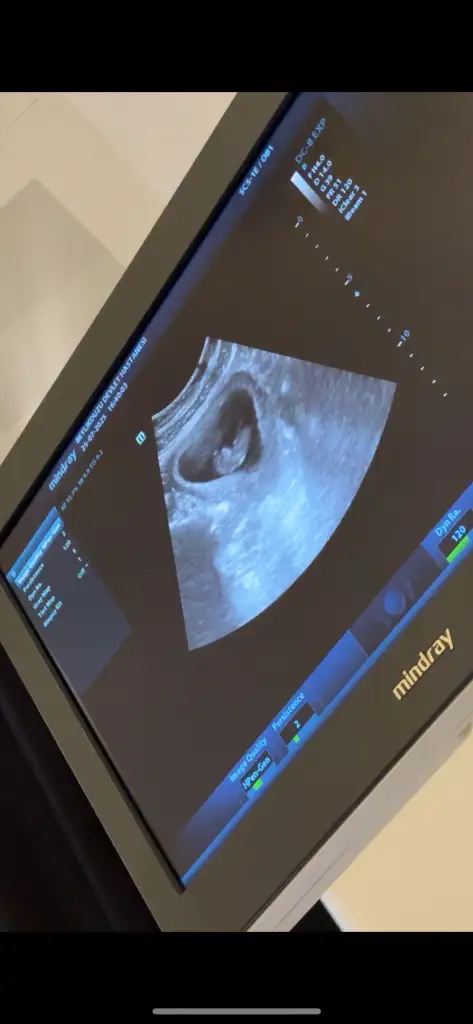

Erkeğe benziyor canımbenim için de bakar mısınız ilki 6 +4 ikinci fotoğraf 8+3 sonuncusu 10+1 Eki Görüntüle 3623528 Eki Görüntüle 3623526 Eki Görüntüle 3623525